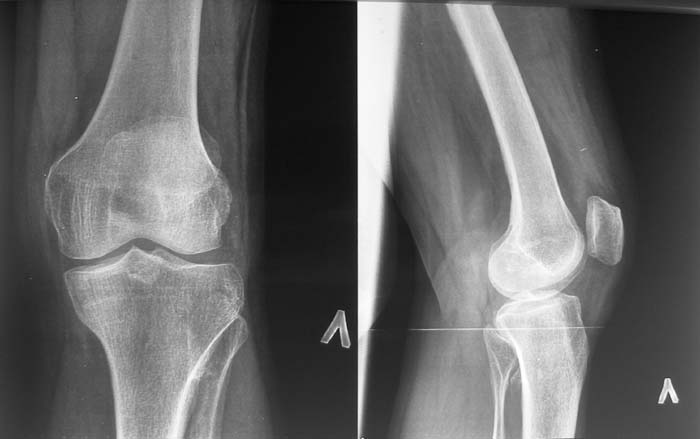

Женщина, 55 лет. С 2002 года - гонартроз. В настоящее время - боли в коленном суставе, стартовые боли, иногда в ночное время (проходит <от перемены положения ноги>).

Принимает НПВС, артрон-комплекс, внутрисуставно гиалган. Ревмопробы отрицательные. На рентгенограмме отметили сужение шейки малоберцовой кости, на спиральной КТ - экзостоз? Ваше мнение о целесообразности операции (велика вероятность повреждения нервов), предварительной биопсии?Спасибо! С уважением, А.В.Владзимирский Донецкий НИИ травматологии и ортопедии Донецк, Украина

Если боли связаны с гонартрозом, то показано тотальное эндопротезирование коленного сустава. Тип эндопротеза - мыщелковый, с сохранением задней крестовидной связки, сейчас таких моделей много (LCS, Balansis, Genesis, Scorpio, КЭКС-01 и другие, всё зависит с какими фирмами Вы работаете). Вопрос об удалении остеохондромы спорный, с одной стороны маловероятно ожидать у женщины 55 лет быстрого перерождения во вторичную хондросаркому при такой рентгенологической картине. Можно спротезировать коленный сустав и проводить рентгенконтроль каждые 6-12 мес. С другой стороны, если спротезировать и оставить остеохондрому, а она начнёт интенсивно рости, то её последующее радикальное удаление может ослабить тибиальный компонент эндопротеза. Проявляя онкологическую настороженность, остеохондрому лучше удалить первым этапом, до эндопротезирования с интервалом между операциями 6 мес. Производить биопсию в данном случае однозначно не целесообразно, так как при перерождении остеохондромы во вторичную хондросаркому на начальных стадиях малигнизации трудно гистологически отличить "добро" от "зла", и в этих ситуациях приоритет отдаётся рентгенологическим признакам. Техника операций при подобной остеохондроме стандартная - краевая резекция. Опасность повреждения малоберцового нерва существует всегда, но она зависит от мастерства хирурга и наличия микрохирургической техники (микроскоп не обязателен :)).

Насчет протезирования коленного сустава - при таком сохранном суставе навряд ли можно согласиться и совершенно согласен с Яковом, что надо искать источника боли сканированием или магнеторезонансными исследованиями.

Действительно, надо бы определиться в причине болевого синдрома. Подобные остеомы, как правило, немые. Болевой синдром может быть связан с околосуставнойт патолоией (например, поражение "гусиной лапки") или внутрисуставной. По R - граммам сустав очень даже сохранный (протезировать его явно нет необходимости), а отвергнуть внутрисуставную патологию или сразу ее максимально устранить поможет артроскопическое вмешательство. Повреждения менисков частенько симулируют остеоартроз.

Суставная щель на вид очень даже приличная. Мне кажется у больной есть варусная деформация колена, и возмможно с этим связано дегенаративное поражение медиального мениска и вся клиническая картина. Если это так, то эндопртезирование это слишком! Может что полегче: артроскопия и медиальная плюс-остеотомия.